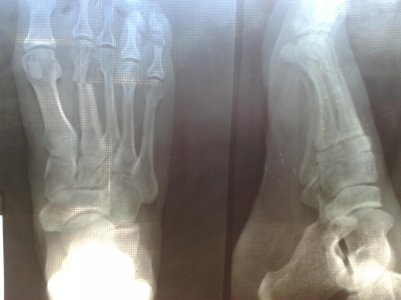

Дбрый день, необходима консультация

поставили диагноз, закрытый перелом основания 5 плюсневой кости левой стопы со смещением.

Предлагают делать операцию, как думаете стоит ли, или можно обойтись и без нее.

Вложения

• 111_00.jpg

Если возраст молодой, физическая активность высокая - лучше оперировать. Можно не оперировать, если не планируете футбол...